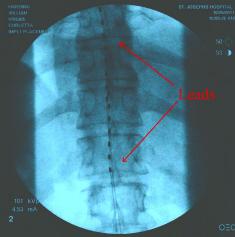

Surgery 16 (Pain Control)

After a number of years dealing with the pain resulting from the left leg below the knee amputation and damage that was residual in Liam’s

left buttocks (where his pelvis decelerated into the soft tissue), Liam decided that it was time to take a larger step in reducing the pain. Liam had

tried drugs as prescribed by his doctors, tried various vitamin injections into the damaged nerves (to repair those nerves), and Liam even tried

injections directly into the nerves along his spinal column, but nothing appeared to work for more than a few moments. So Liam had a Medtronic

RestoreUltra® implanted... Before the final implant was made Liam went through a device trial, to determine the feasibility of the final implant. The

RestoreUltra® is a multi-programmable, rechargeable neurostimulator that is part of a spinal cord stimulation system. The components that make